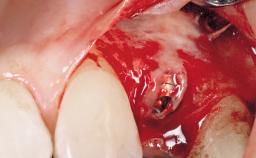

A 42-year-old female patient was referred to our clinic at the School of Dentistry of the University of São Paulo in November 2004, presenting a deficient restoration in the upper left central incisor. The clinical examination revealed no gingival retraction or any signs of gingival inflammation and, therefore, previous periodontal treatment was not considered. The patient presented a high lip line at full smile and a thin tissue biotype. This combination characterized a high-risk situation from an anatomic point of view, which required careful preoperative planning and cautious surgical execution.

Placement Protocol Immediate implant placement

Tooth Site Maxillary incisor or canine

Socket Morphology Single-root socket

Socket Integrity Sufficient, with intact bone walls